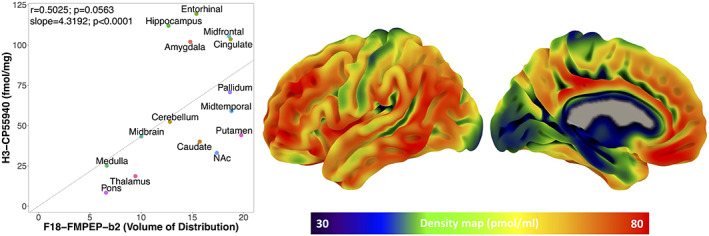

Mean distribution of F18‐FMPEP‐d2 PET scans from 36 subjects is visualized in Figure 1. The distribution of CNR1 mRNA expression and V T of F18‐FMPEP‐d2 PET from each ROI is shown in Figure 2. Strong auto‐correlation was observed both for V T from F18‐FMPEP‐d2 PET scans (inter‐subject: mean correlation coefficient rho: .8674) and for CNR1 mRNA expression from the Allen Human Brain Atlas (inter‐probe: mean correlation coefficient rho = .9148), which ensures consistency of observations. Between V T of F18‐FMPEP‐d2 PET scans and CNR1 mRNA expression from 18 ROIs, moderate strength of correlation was observed (rho = .5067, p = .0337). The correlation between V T of F18‐FMPEP‐d2 PET scans and mRNA was significant in subcortical regions (rho = .8182, p = .0068), not in cortical regions (rho = .5952, p = .1323). Strong positive correlation was also found between CNR1 mRNA expression and H3‐CP55940 binding from 11 ROIs (r = .6336, p = .0364), which validates the finding between F18‐FMPEP‐d2 PET scans and CNR1 mRNA (Figure 3). The correlation between V T of F18‐FMPEP‐d2 PET scans and H3‐CP55940 binding from 15 ROIs was not significant (r = .5025, p = .0563). The slope estimates (slope = 4.3192; p < .0001) of the regression were used to transform F18‐FMPEP‐d2 PET atlas into density map atlas (Figure 4, https://neurovault.org/images/782713/).

Our main finding was that CNR1 mRNA expression was moderate to strongly correlated with CB1 receptor availability from V T of F18‐FMPEP‐d2 PET, showing the association of CNR1 mRNA expression with CB1 receptor. The correlation between V T of F18‐FMPEP‐d2 PET scans and H3‐CP55940 binding was marginally significant, and density map atlas of CB1 receptor was produced. From the meta‐analysis, the moderate to strong correlation was observed between mRNA expression from the Allen Human Brain Atlas and protein expressions from PET/SPECT scans across multiple genes, with the pooled correlation coefficient of .76, which was stronger than the correlation coefficient of .5067 between F18‐FMPEP‐d2 PET scans and CNR1 mRNA in this study.

The association between CNR1 mRNA expression and protein expression from either PET scans or autoradiography showed the moderate to strong correlation, despite samples stemming from unrelated populations. However, we also have to consider that there are many complex and various post‐transcriptional mechanisms that are involved in turning mRNA into protein (Rizzo et al., ref. 2016). mRNA transcripts interact with intra, extracellular stimuli, and are modified, regulated by non‐coding RNAs (Di Liegro et al., ref. 2014), which have an influence on protein expression for each cell type (Cheng et al., ref. 2005; Rizzo et al., ref. 2014). In addition, technologies regarding measurement of either mRNA or protein expression may not be perfectly accurate (Veronese et al., ref. 2016). Calculation of mRNA expression for each probe has its advantages and disadvantages (Arnatkeviciute et al., ref. 2019). Therefore, probe selection has an impact on the final results of mRNA expression (Arnatkeviciute et al., ref. 2019). In this study, we selected the median gene expression within each ROI to minimize the possible bias from probes. Also, mRNA expression is analyzed in the cytoplasm, while CB1 receptor is predominantly expressed in the cell membrane, presynaptically (Mechoulam & Parker, ref. 2013). However, genomic atlas does not provide an accurate mapping at a cellular level, and mRNA expression as well as protein expressions from PET scans and autoradiography are averaged within each ROI, yielding representative expression values. Also, autoradiography provides far less spatial information than other technologies (Beliveau et al., ref. 2017) and can be acquired only from postmortem states. These differences in PET scans and autoradiography might affect non‐significant association between V T of F18‐FMPEP‐d2 PET scans and H3‐CP55940 binding.

Previously, the association of brain mRNA mappings of the Allen Human Brain Atlas with several PET‐derived protein expressions has been investigated, including serotonin receptors (Beliveau et al., ref. 2017; Komorowski et al., ref. 2017; Rizzo et al., ref. 2014), serotonin transporters (Beliveau et al., ref. 2017; Komorowski et al., ref. 2017), opioid receptors (Rizzo et al., ref. 2014), dopamine receptors (Komorowski et al., ref. 2020), and monoamine oxidase A (MAO‐A) (Komorowski et al., ref. 2017; Zanotti‐Fregonara et al., ref. 2014). The correlation coefficient ranged from −.10 between 5‐HTT mRNA and C11‐DASB PET to .99 between GRM1 mRNA and F18‐FIMX PET. We included one result with the strongest correlation between each radiopharmaceutical from single institution with one mRNA expression, as several studies report the association between a single radiopharmaceutical with several mRNAs. The presently observed correlations for CB1 (rho = .5067, p = .0337) was slightly weaker than the pooled result of this meta‐analysis. Even in the same neurotransmitter system, there was a difference in the associations between mRNA expression and protein expression according to the receptor or transporter. With the same gene expression of HTR1A mRNA from the Allen Human Brain Atlas, a wide range of correlation coefficients with protein expression has been shown; .75–.95, probably due to the characteristics of radiopharmaceuticals and ROIs included in each study. In addition, the majority of the studies included only a small number of subjects, typically <30. However, the moderate to strong correlation was observed between mRNA expression and protein expressions across multiple genes, showing the association of genes with protein levels of human brains. Recently, Hansen et al. reported the correlation between mRNA expression and multiple neurotransmitter receptors and transporters including CB1 receptor (Justine et al., ref. 2022). Poor spatial correspondences between mRNA expression and protein expression from PET scans were observed, except for 5 metabotropic receptors including CB1 receptor with a correlation coefficient of .66 (Justine et al., ref. 2022). However, their report did not include the relevant autoradiographic finding. In addition, subjects were scanned with the different radiopharmaceutical of C11‐OMAR with this study, making it difficult to compare with our result. There are a number of limitations that should be taken into account. First, F18‐FMPEP‐d2 PET scans were acquired from young males included in previous studies on feeding behavior and obesity (Kantonen, Karjalainen, et al., ref. 2021; Kantonen, Pekkarinen, et al., ref. 2021). Although no effect of age on CB1 receptor was reported in previous studies (Borgan et al., ref. 2019; Hirvonen et al., ref. 2012, ref. 2013), there is a difference in the age of participants between PET scan, autoradiography, and Allen Human Brain Atlas. The sample size of Allen Human Brain Atlas (n = 6) is too small to evaluate the age effect on mRNA expression and to give accurate result of the degree of correlation. In addition, the autoradiography study (Glass et al., ref. 1997) provides the average density of H3‐CP55940 binding in the adult human brain, without the density of each subject. Therefore, age could not be included as a covariate in this study. Second, while making the density atlas map of CB1 receptor, an area devoid of CB1 receptor would be estimated to have positive value of CB1 receptor density. A more accurate estimation for the linear conversion of V T to receptor density would be set the intercept = volume of non‐displaceable uptake. The linear conversion to receptor density will be erroneous for small V T. However, we used V T as the outcome measure to keep the results comparable with previous reports on the same CB1 receptor dataset (Kantonen, Karjalainen, et al., ref. 2021; Kantonen, Pekkarinen, et al., ref. 2021). Third, the method of calculation of mRNA expression from the Allen Human Brain Atlas and V T of F18‐FMPEP‐d2 PET might have an impact on the final results of this study. Further studies are needed to examine the association between protein expression based on multiple PET radioligands and gene expression with a uniform method.

In conclusion, we observed the moderate to strong associations between gene and protein expression for CB1 receptor in the human brain. Also, this association between CNR1 mRNA and CB1 receptor protein expression was validated by autoradiography. We combined the autoradiographic finding with PET of CB1 receptor, producing the density atlas map of CB1 receptor for the first time in the human brain. There have been multiple studies investigating the association between mRNA and protein expression in the human brain, showing the heterogeneous results; however, the moderate to strong correlation was observed between mRNA expression and protein expressions across multiple genes, showing the significant association of genes with protein levels. Further study is needed to investigate the relationship between multiple genes and in vivo proteins to improve and accelerate drug development.